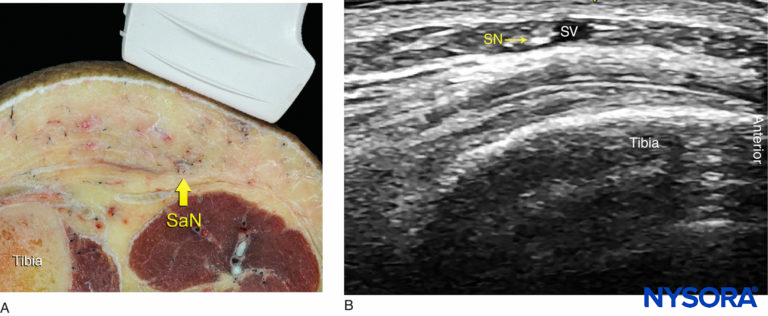

- Below the knee, the saphenous nerve passes along the tibial side of the leg, adjacent to the great saphenous vein subcutaneously (Figure 4).

FIGURE 4. (A) Cross-sectional anatomy of the saphenous nerve (SaN) at the level of the tibial tuberosity. (B) US image of the SaN below the knee. The SaN is seen within the immediate vicinity of the great saphenous vein (SV). The transducer should be applied lightly to avoid compression of the SV because the vein serves as an important landmark for the technique.